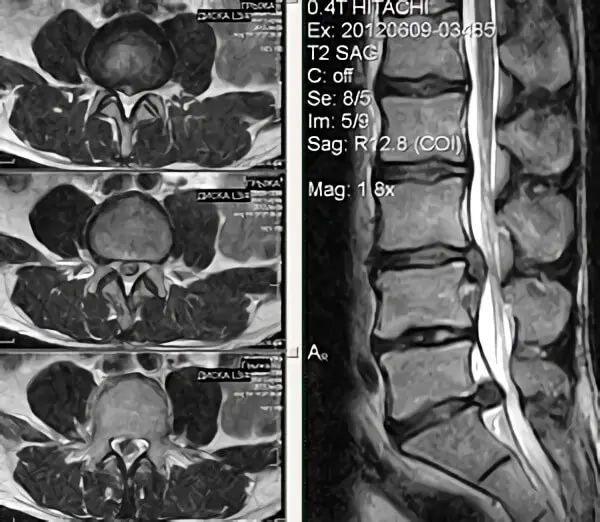

Грижа або протрузія диска діагностується за допомогою МРТ або УЗД хребта. Обов’язковим є облік неврологічного статусу хворого для планування подальшого лікування (хірургічного або консервативного). Слід пам’ятати, що при КТ або МРТ можуть бути неточності, облік яких дозволить уникнути операції.